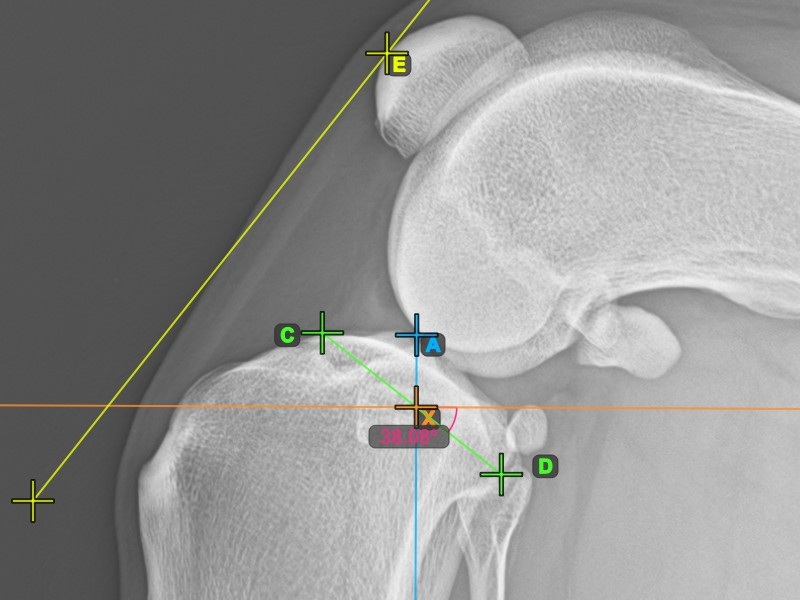

Complete the TPA Angle by marking the most caudal point of the tibial head (tibial plateau). The TPA Angle is automatically calculated as the angle between the line connecting the two points on the tibial plateau and the perpendicular line to the long axis of the tibia.

The image below depicts the usual placement of the most caudal point on the tibial plateau and the automatically calculated TPA Angle measurement.